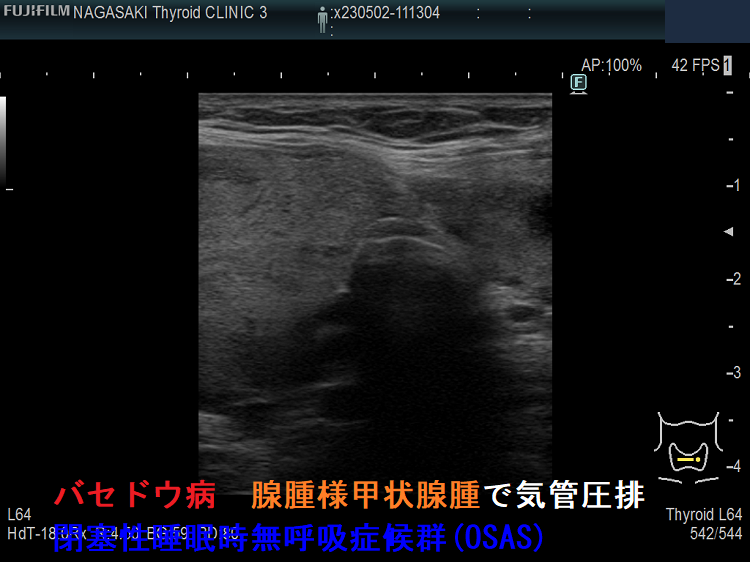

バセドウ病を基盤とする腺腫様甲状腺腫で閉塞性睡眠時無呼吸症候群(OSAS) 超音波(エコー)画像;抗甲状腺薬 メルカゾールで甲状腺機能は安定していても甲状腺全摘手術になります。

ケース④